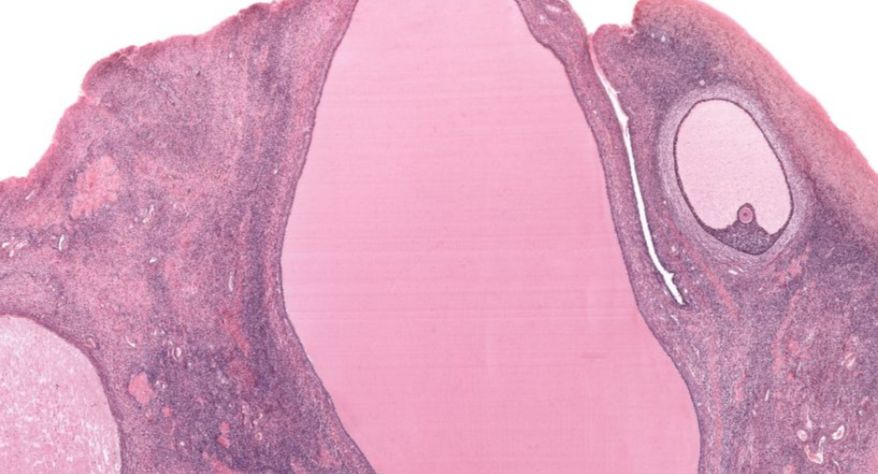

低倍镜:区分卵巢的皮质及髓质,皮质有不同时期发育的卵泡分布于其中,髓质为结缔组织及丰富的血管构成。着重观察皮质内不同发育阶段的各级卵泡及闭锁卵泡、黄体和卵泡间的结缔组织。高倍镜:重点观察各级卵泡。

1.全景图

2.被膜

3.皮质

4.原始卵泡

5.初级卵泡

6.次级卵泡

8.成熟卵泡

9.卵母细胞